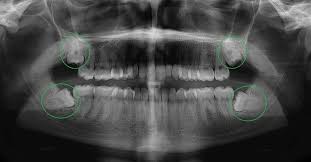

NHỔ RĂNG KHÔN MỌC LỆCH

NHỔ RĂNG KHÔN